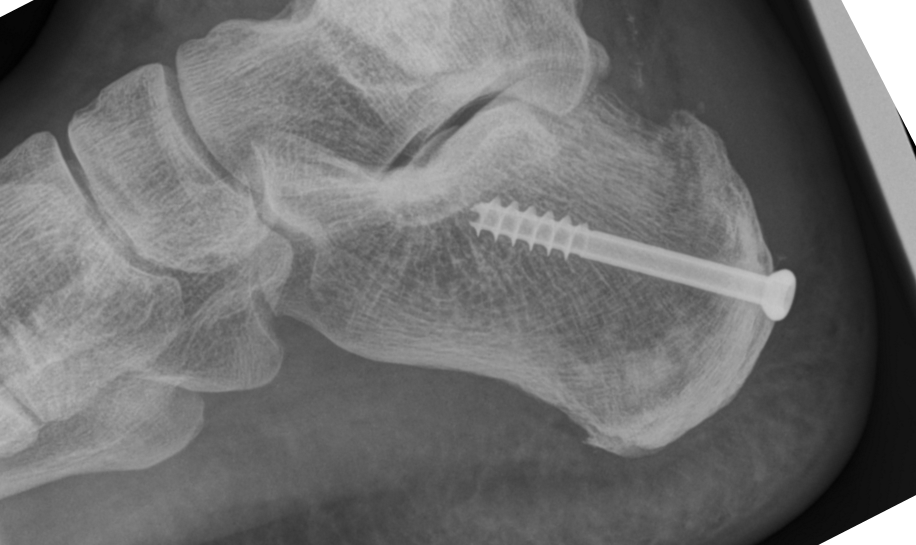

Alles aufgeräumt, Exostose entfernt und einen Keil aus dem Fersenbein herrausgesägt und die Ferse angeklappt und verschraubt. Der Sehnenansatz bleibt unverändert.

Der Knochen ist zusammengewachsen und ich darf voll belasten.

In den Bildern sieht man ganz gut wie der obere Teil des Fersenbeins durch das Anklappen kürzer ist.